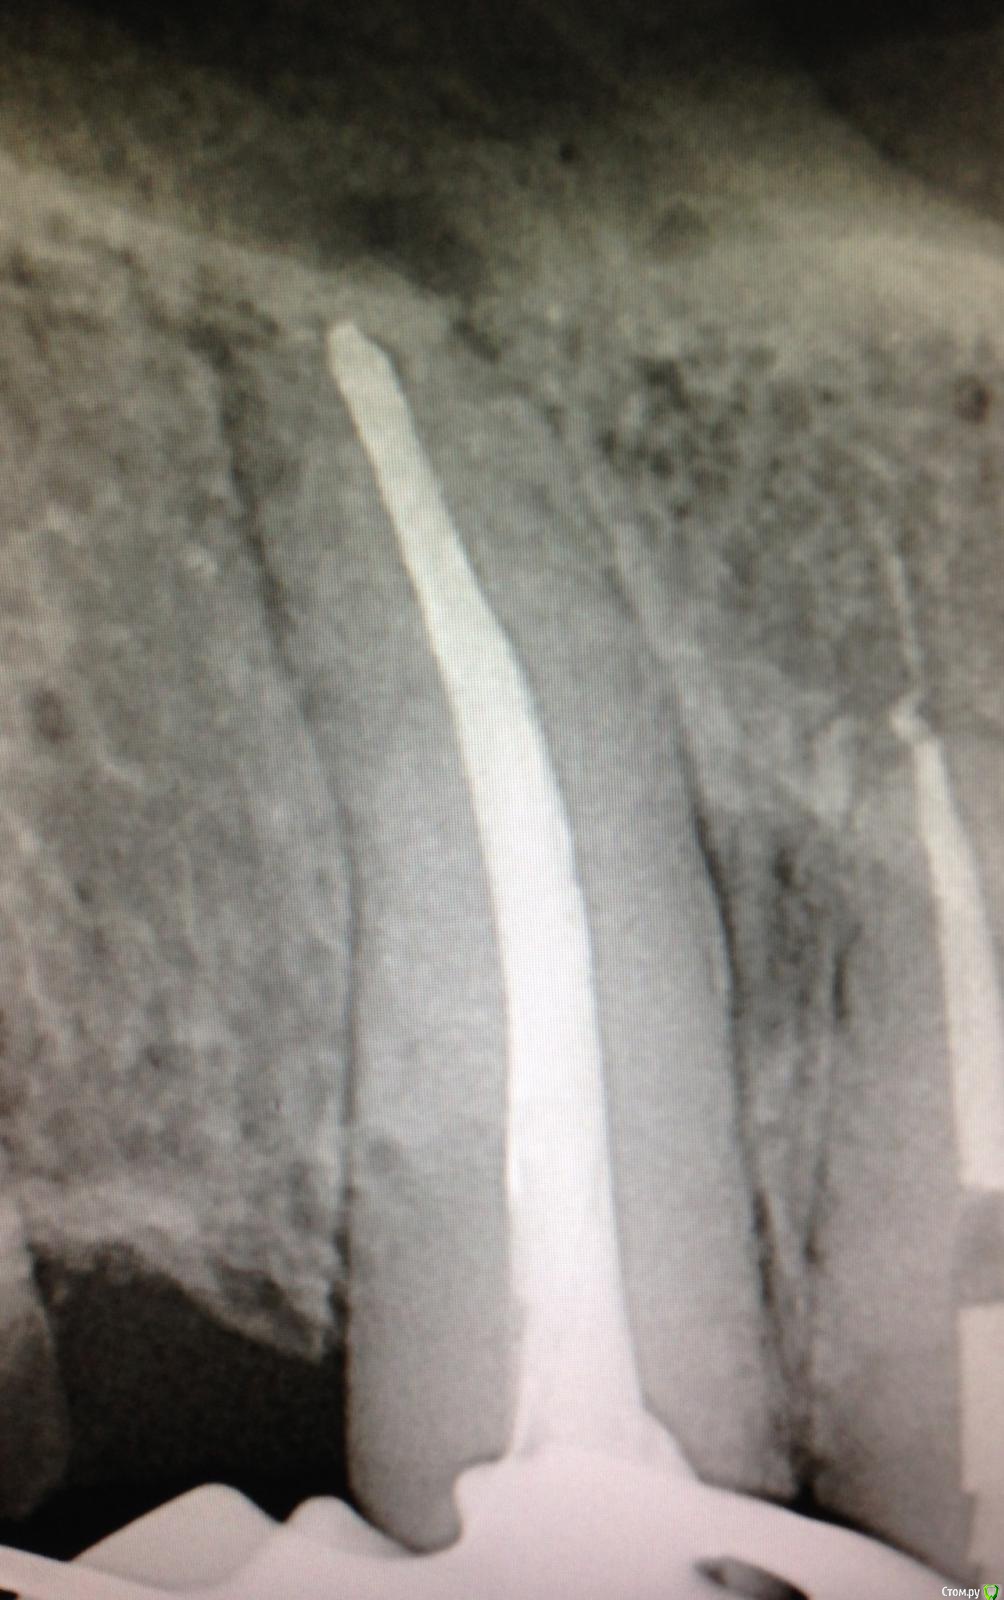

SSTi Опубликовано 7 января, 2015 Автор Поделиться Опубликовано 7 января, 2015 21 запаковал. 4 Ссылка на комментарий

Shaid Опубликовано 10 января, 2015 Поделиться Опубликовано 10 января, 2015 Серега, чем паковал на последнем снимке? Сегодня пришла пациентка с таким же зубом. Апекс 80, если не больше. Пока на кальции. Думаю как паковать..без увеличения, плагеров, коллаг.губки. Ссылка на комментарий

SSTi Опубликовано 12 января, 2015 Автор Поделиться Опубликовано 12 января, 2015 Триокси кончился. Гуттой. Латералка. Нарезал уступ и халатералил. Чем еще. У меня ограниченный инвентарь) к сожалению. Ссылка на комментарий